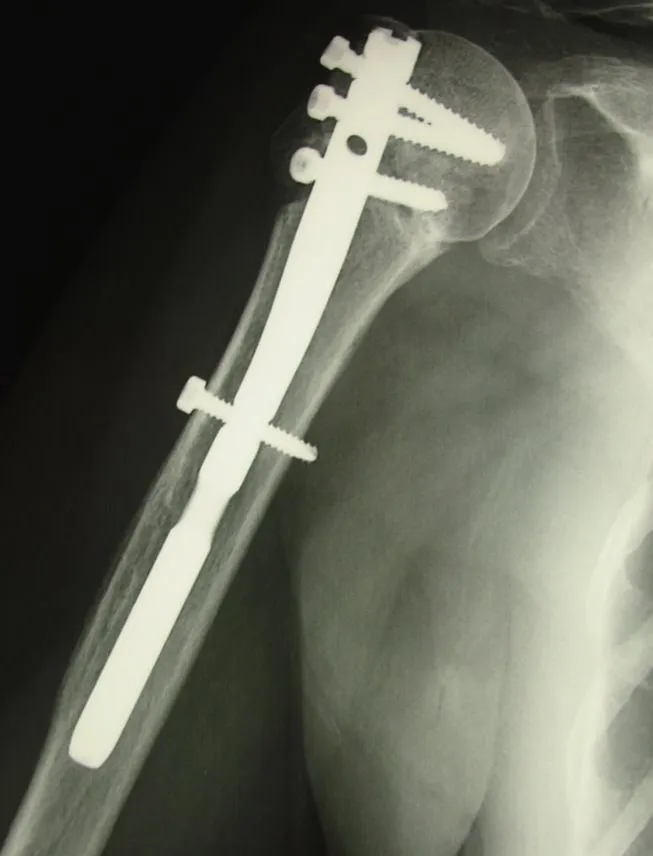

- une ostéosynthèse ; c'est a dire le repositionnement et la fixation des fragments osseux) . Cette ostéosynthèse peut faire appele à differents types de matériel : clou centro-médullaire, vis etc... L'intervention est réalisée le plus souvent sous anesthésie loco-régionale ( seul votre bras est endormi ) et sous contrôle radiographique, ce qui permet au chirurgien d'avoir un contrôle parfait du positionnement du matériel et de la qualité de la réduction chirurgicale. Après l'intervention le bras est immobilisé dans une attelle coude au corps pour une période de 3 à 6 semaines. La rééducation est généralement débutée à partir de la 3eme semaine chez un kinésitherapeute de ville. la rééducation est longue et demande une étroite collaboration entre le patient et le kinésithérapeute sous le contrôle du chirurgien.

fracture neer 4

enclouage fracture 4 fragments épaule